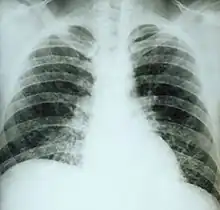

Chest X-ray of a patient with acute pulmonary histoplasmosis

Clinically, a wide spectrum of disease manifestations occurs, making diagnosis somewhat difficult. More severe forms include the chronic pulmonary form, often occurring in the presence of underlying pulmonary disease, and a disseminated form, which is characterized by the progressive spread of infection to extrapulmonary sites. Oral manifestations have been reported as the main complaint of the disseminated forms, leading the patient to seek treatment, whereas pulmonary symptoms in disseminated disease may be mild or even misinterpreted as flu.[20] Histoplasmosis can be diagnosed by samples containing the fungus taken from sputum (via bronchoalveolar lavage), blood, or infected organs. It can also be diagnosed by detection of antigens in blood or urine samples by ELISA or polymerase chain reaction. Antigens can cross-react with antigens of African histoplasmosis (caused by Histoplasma duboisii), blastomycosis, coccidioidomycosis, paracoccidioidomycosis, and talaromycosis infection. Histoplasmosis can also be diagnosed by a test for antibodies against Histoplasma in the blood. Histoplasma skin tests indicate whether persons have been exposed, but do not indicate whether they have the disease.[4] Formal histoplasmosis diagnoses are often confirmed only by culturing the fungus directly.[5] Sabouraud agar is one agar growth medium on which the fungus can be cultured. Cutaneous manifestations of disseminated disease are diverse and often present as a nondescript rash with systemic complaints. Diagnosis is best established by urine antigen testing, as blood cultures may take up to 6 weeks for diagnostic growth to occur and serum antigen testing often comes back with a false negative before 4 weeks of disseminated infection.[21]